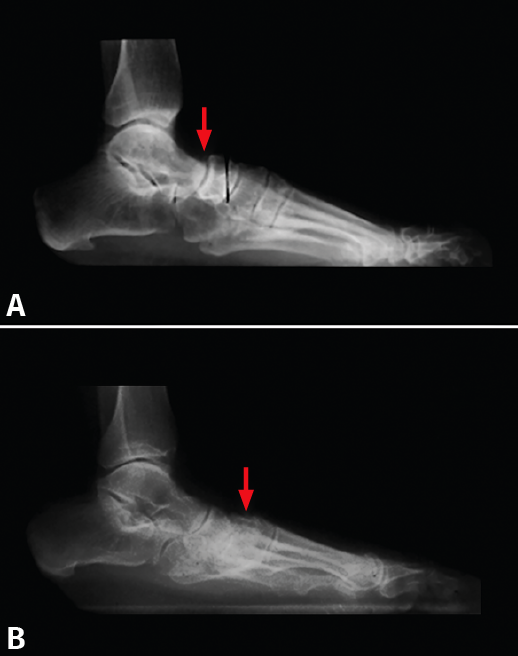

Figura 4. Pie plano por disfunción del tibial posterior. La flecha señala: A: subluxación talonavicular; B: subluxación navículo-cuneiforme medial.

Ello fue motivo de una presentación el año 1996 en la Societat Catalana de Cirurgia Ortopèdica i Traumatologia por A. Viladot Voegeli et al.(7), que estudiaron este tema: se analizaron las radiografías de perfil en carga de 30 pies planos secundarios a una disfunción del tibial posterior. Se pudo observar que 10 pies (33%) presentaban una subluxación talonavicular. En 11 pies (37%) la subluxación se encontró entre el navicular y el CM (Figura 4) y 2 pies (7%) presentaban una pequeña subluxación mixta entre el talus, el navicular, el CM y el primer metatarsiano. Por último, 7 pies (23%) no presentaban ningún tipo de alteración en la congruencia articular.

Cuando el tibial posterior claudica, si el ligamento calcaneonavicular plantar resiste, el arco longitudinal se colapsa distalmente a nivel de la articulación navículo-cuneiforme medial y/o 1.ª ATMT. En estos casos, la línea de Meary se rompe habitualmente en la articulación navículo-cuneiforme medial. Cuando el ligamento calcaneonavicular plantar también cede, falla el suelo de la coxa pedis y la cabeza del talus cae hacia abajo, produciéndose la subluxación al nivel de la talonavicular. En estos pacientes, la línea de Meary se rompe a este nivel.